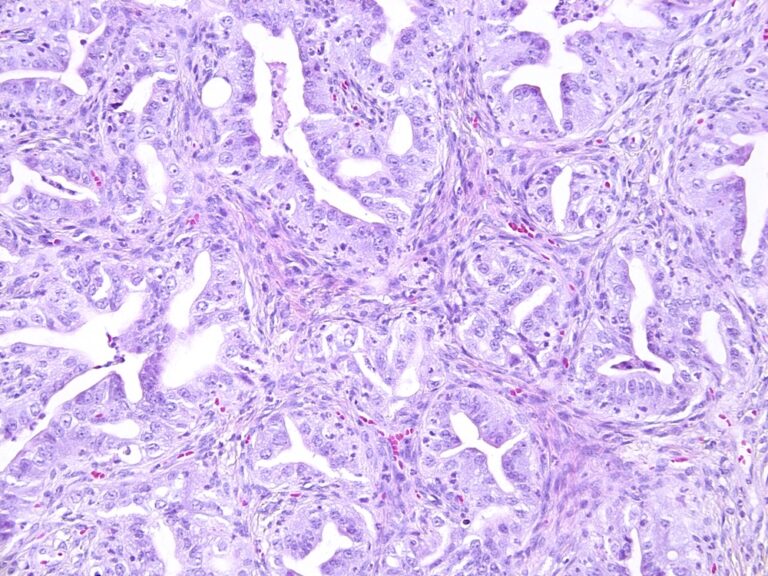

Histology is the study of microscopic anatomy of biological tissues. There are several techniques that can be used to obtain histological slides, each with their own advantages.